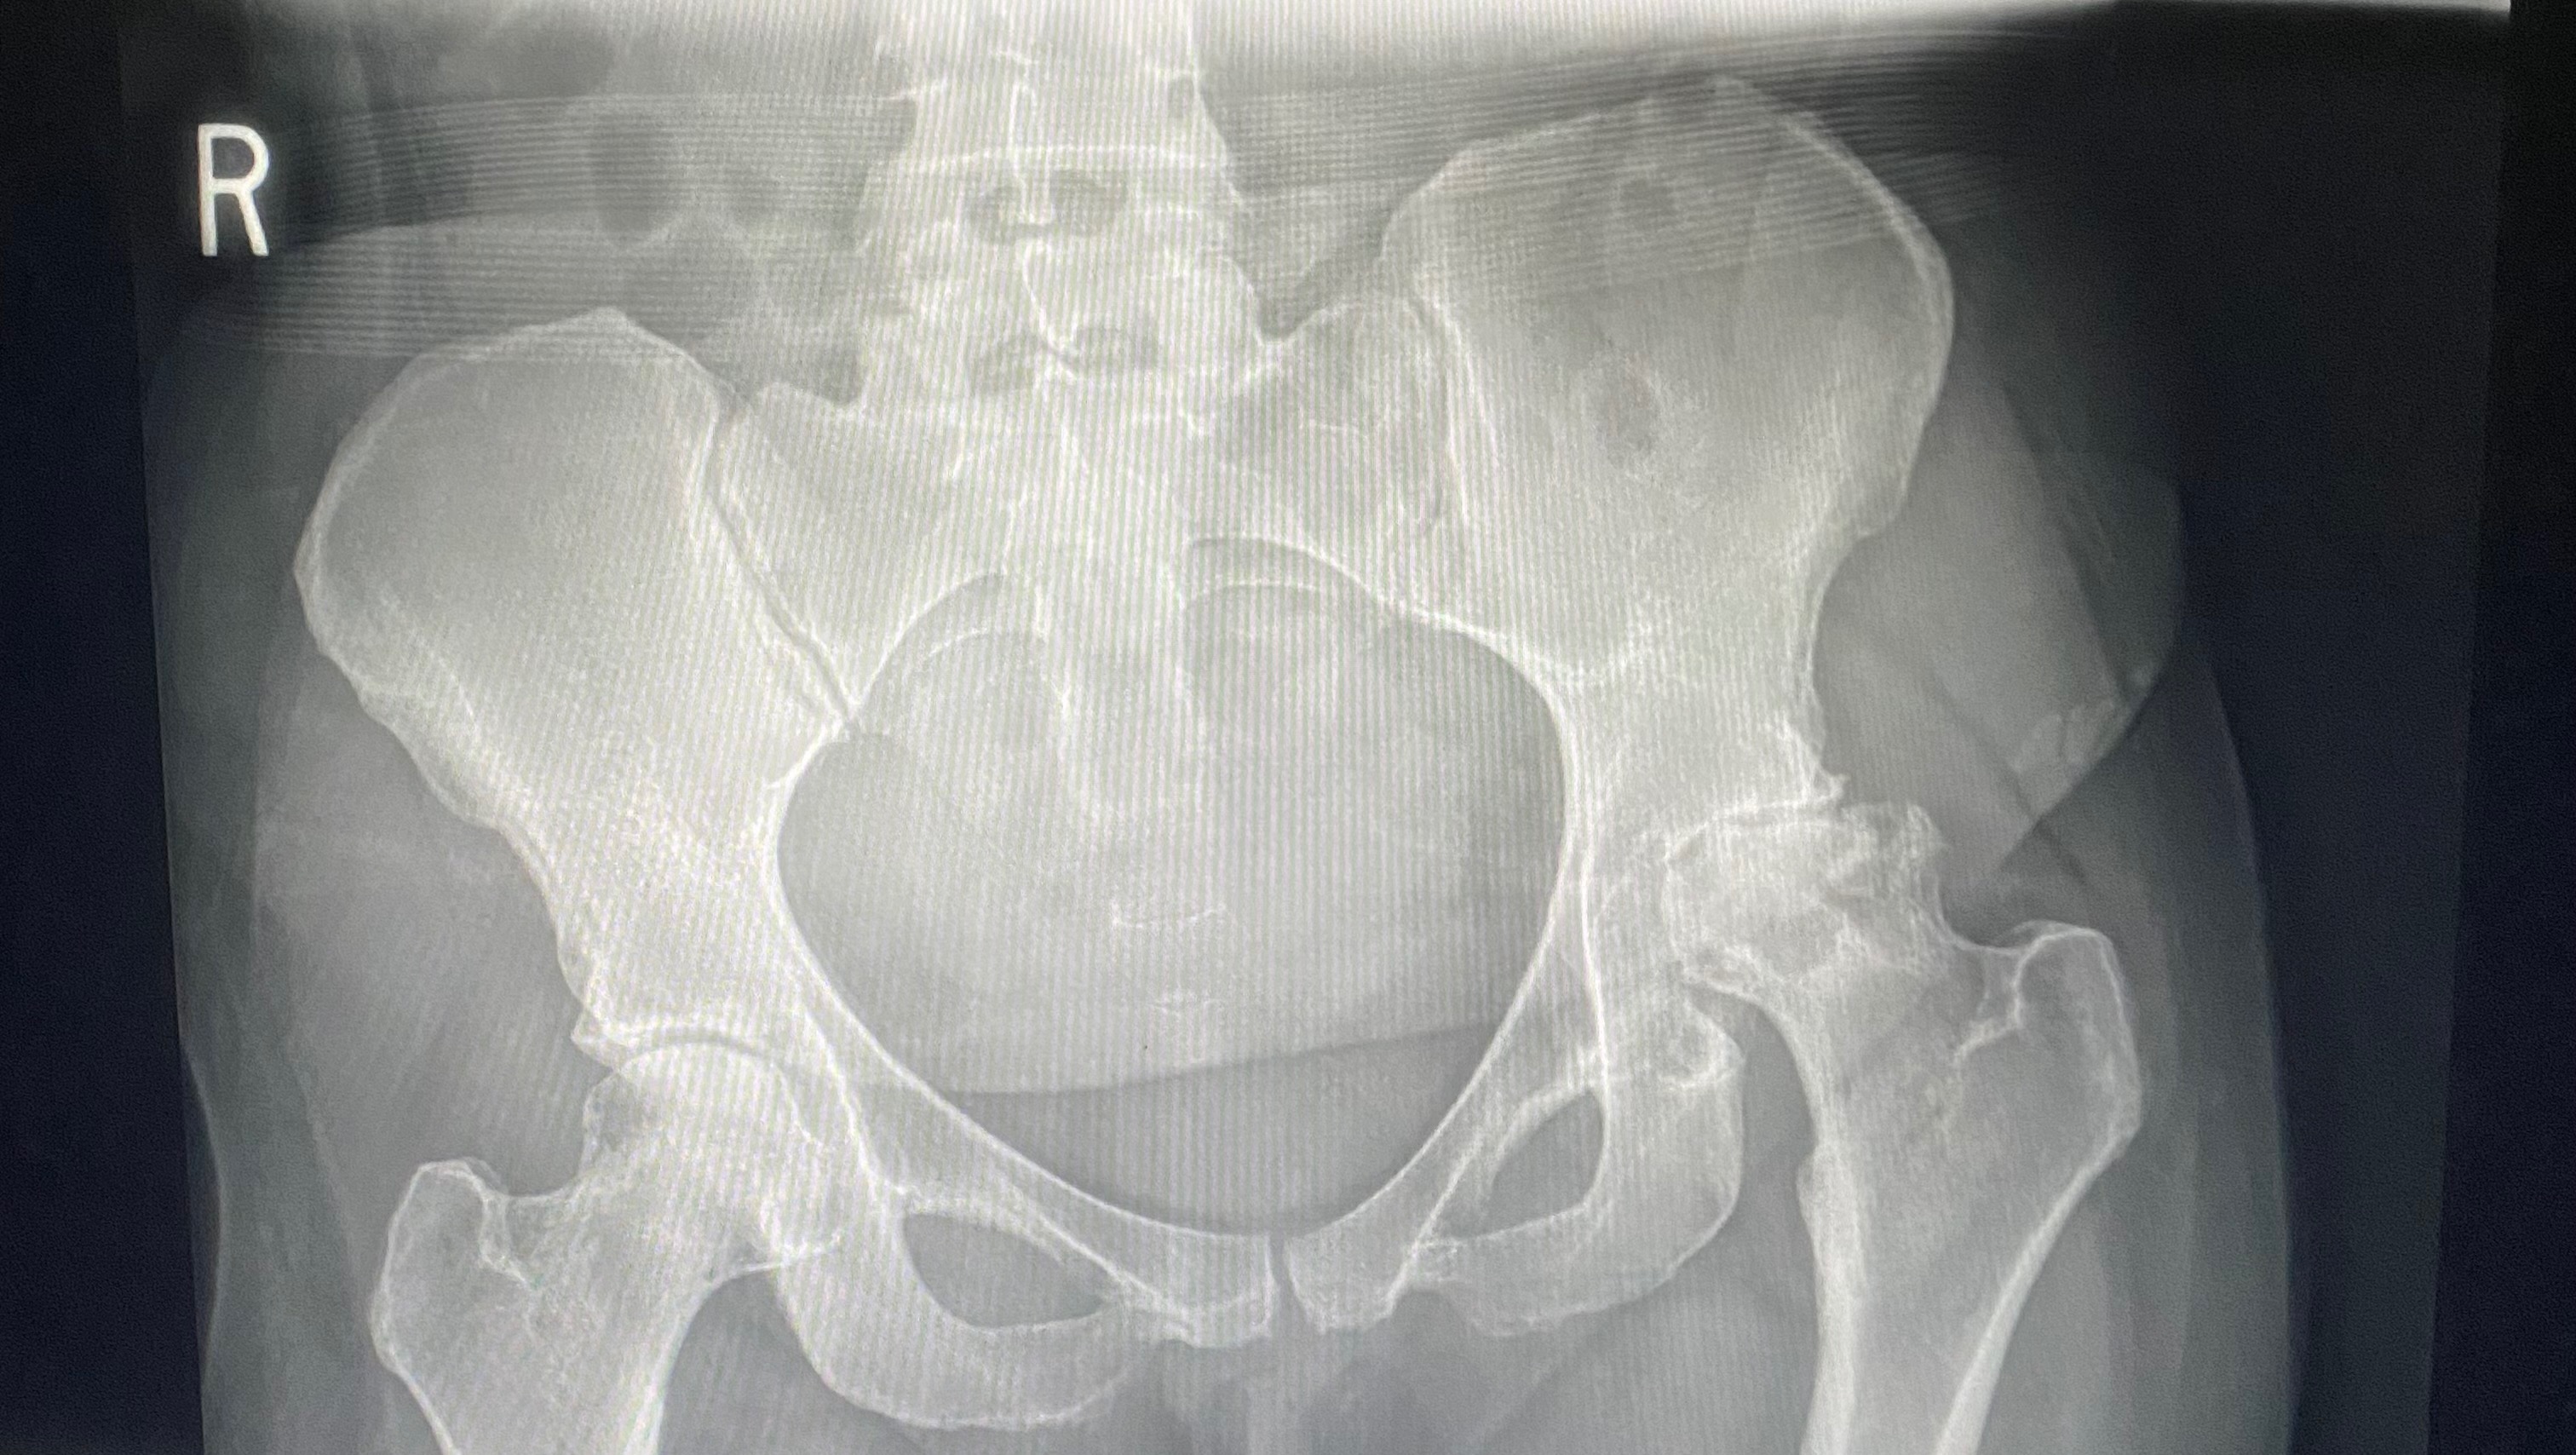

I’ve always had back and hip issues, but I just attributed it to constantly being on my feet 6-12 hours a day, 5-6 days a week; until September 17th when I was officially diagnosed with Avascular Necrosis in my hips. Essentially, both of my hips were not getting any blood supply, causing the bone in my hip joints to die and erode away. It’s extremely painful but, without insurance, all I could do is continue to work and hope that I’d be able to find affordable insurance soon. While my jobs have been as accommodating to me as possible, nobody could have prevented the inevitable.

Sunday, December 7th, I took myself to the ER after trying and failing to get another work day started. I couldn’t take more than 4-5 steps without bursting into tears and after a CT scan was preformed, I learned why. Not only has my left hip eroded almost entirely, my right hip bone was completely hollow inside, causing it to break at least a week or two prior. I had no choice: it was time for surgery, whether I had the insurance or not.